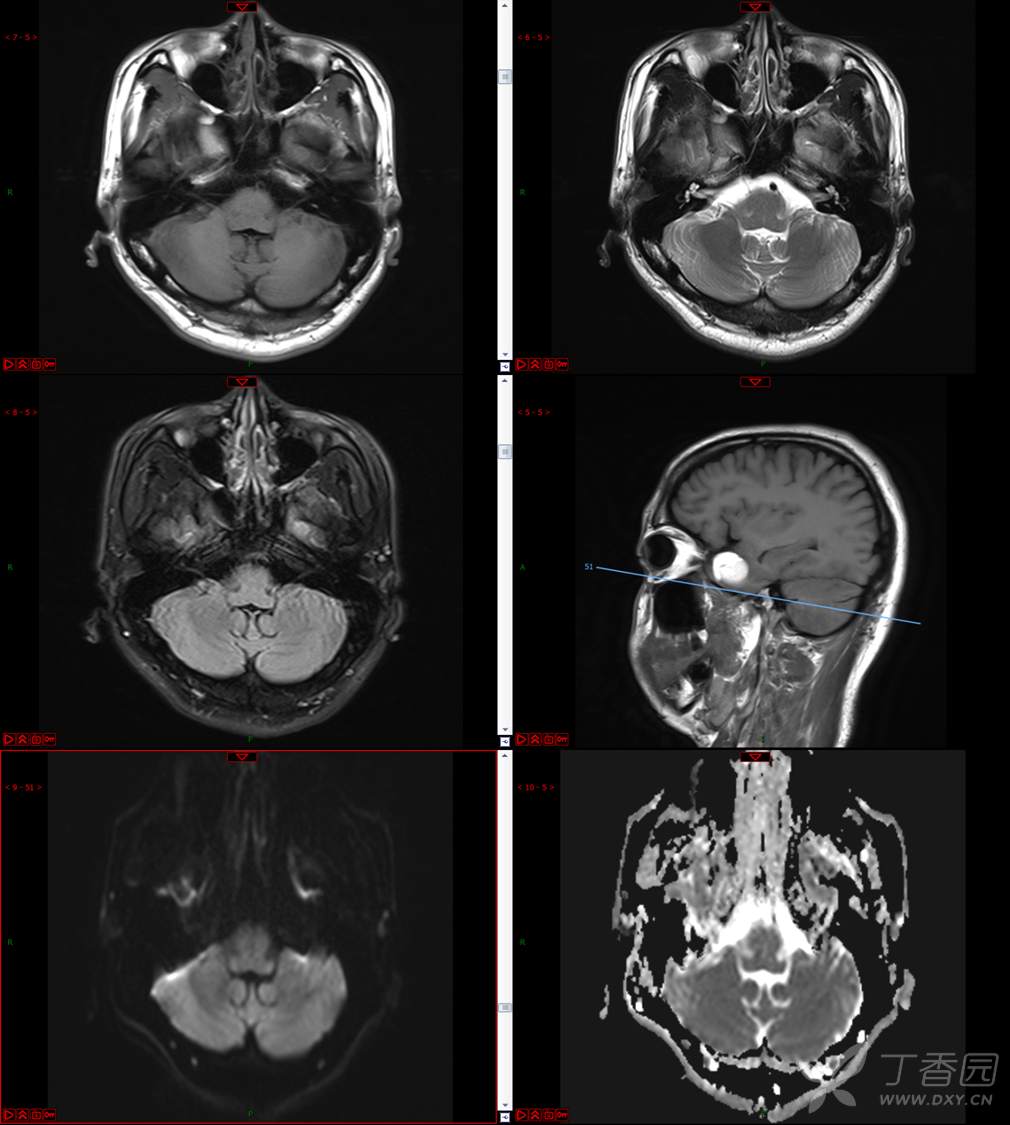

【影诊笔记534】青年男性,视物模糊就诊,CT、MRI、MRS齐全,请分析~~~

主 诉:视物重影5天。

现病史:患者5天前无明显诱因出现视物重影,表现为右视时视物成双,无头痛、头晕,无恶心、呕吐,无面部麻木、饮水呛咳等,于当地医院就诊,行颅脑MR示“颅内占位性病变”,现为求进一步治疗来诊。患者病来精神可,饮食、睡眠正常,体重无明显变化。